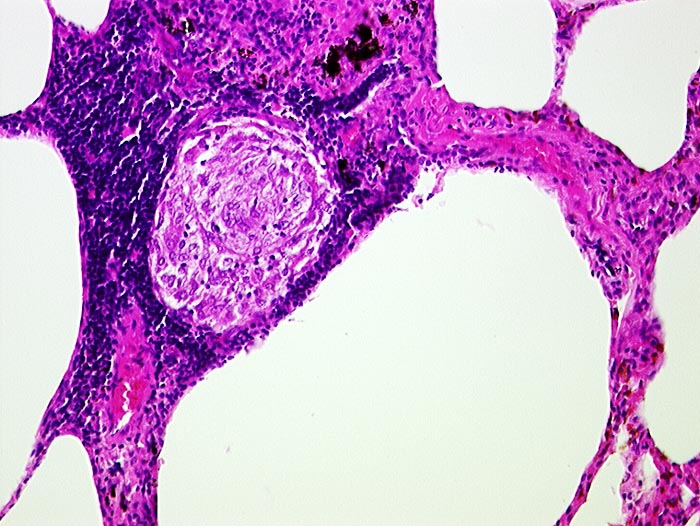

Sarkoidosegranulom

Entzündung / Reparatur

Lunge

Granulom aus Epitheloidzellen umgeben von Lymphozyten in einem Alveolarseptum.

Granulome in Lungen, Bronchialschleimhaut, Leber, Milz und Lymphknoten pulmonal